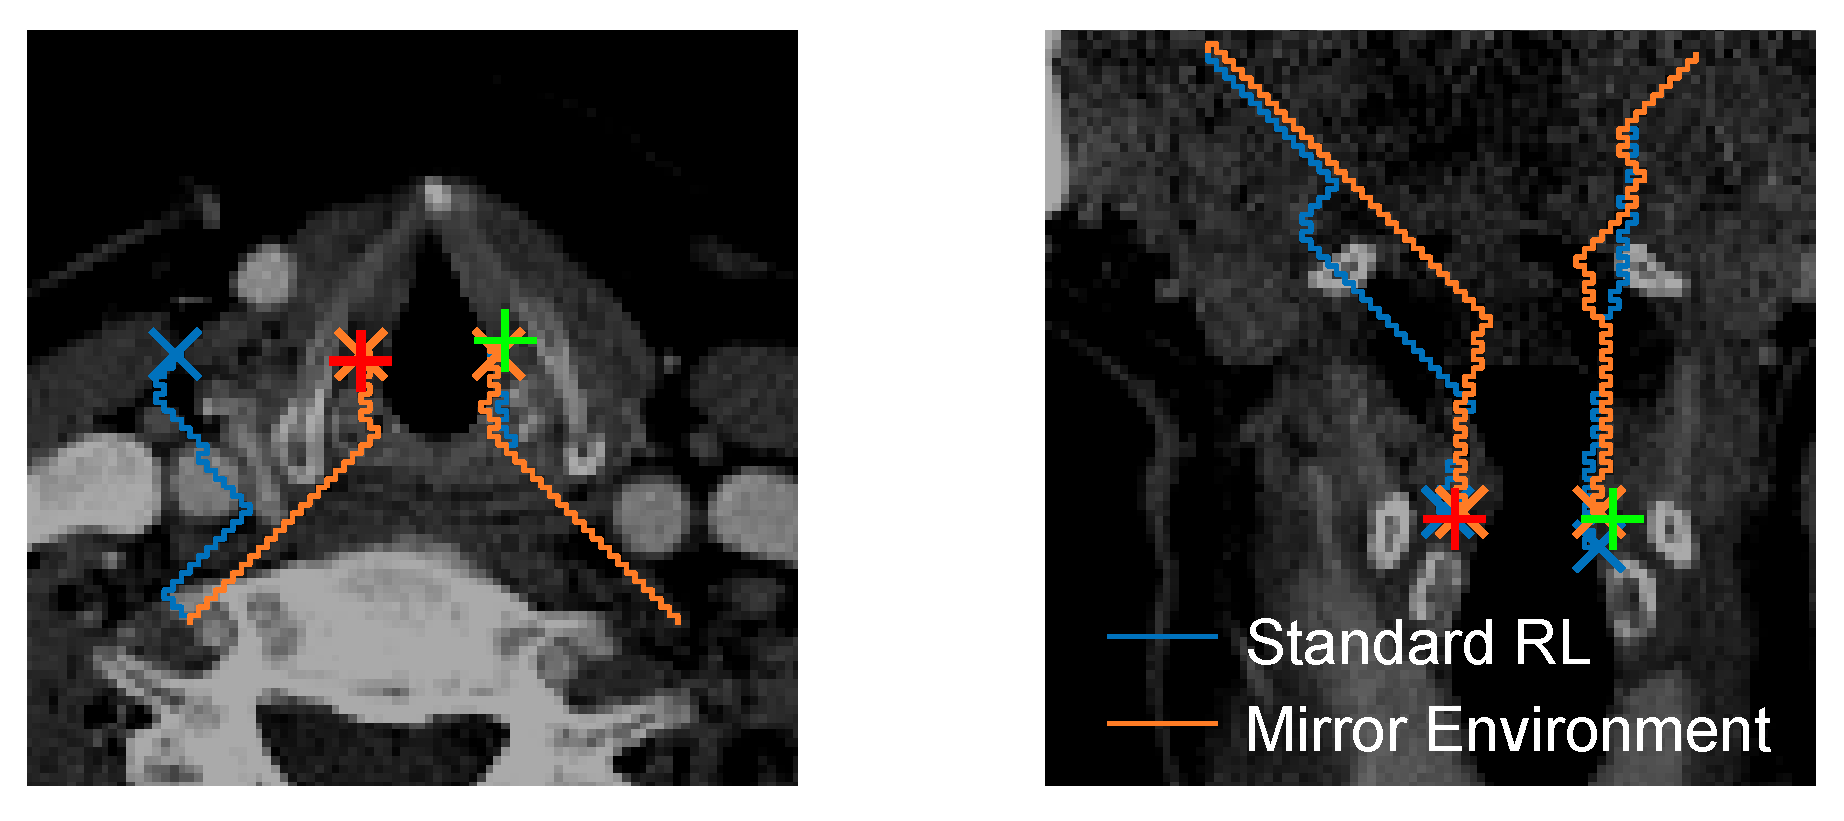

2. Methodology

Mirror Environment

3.3. Training Efficiency

3.4. Localization Performance